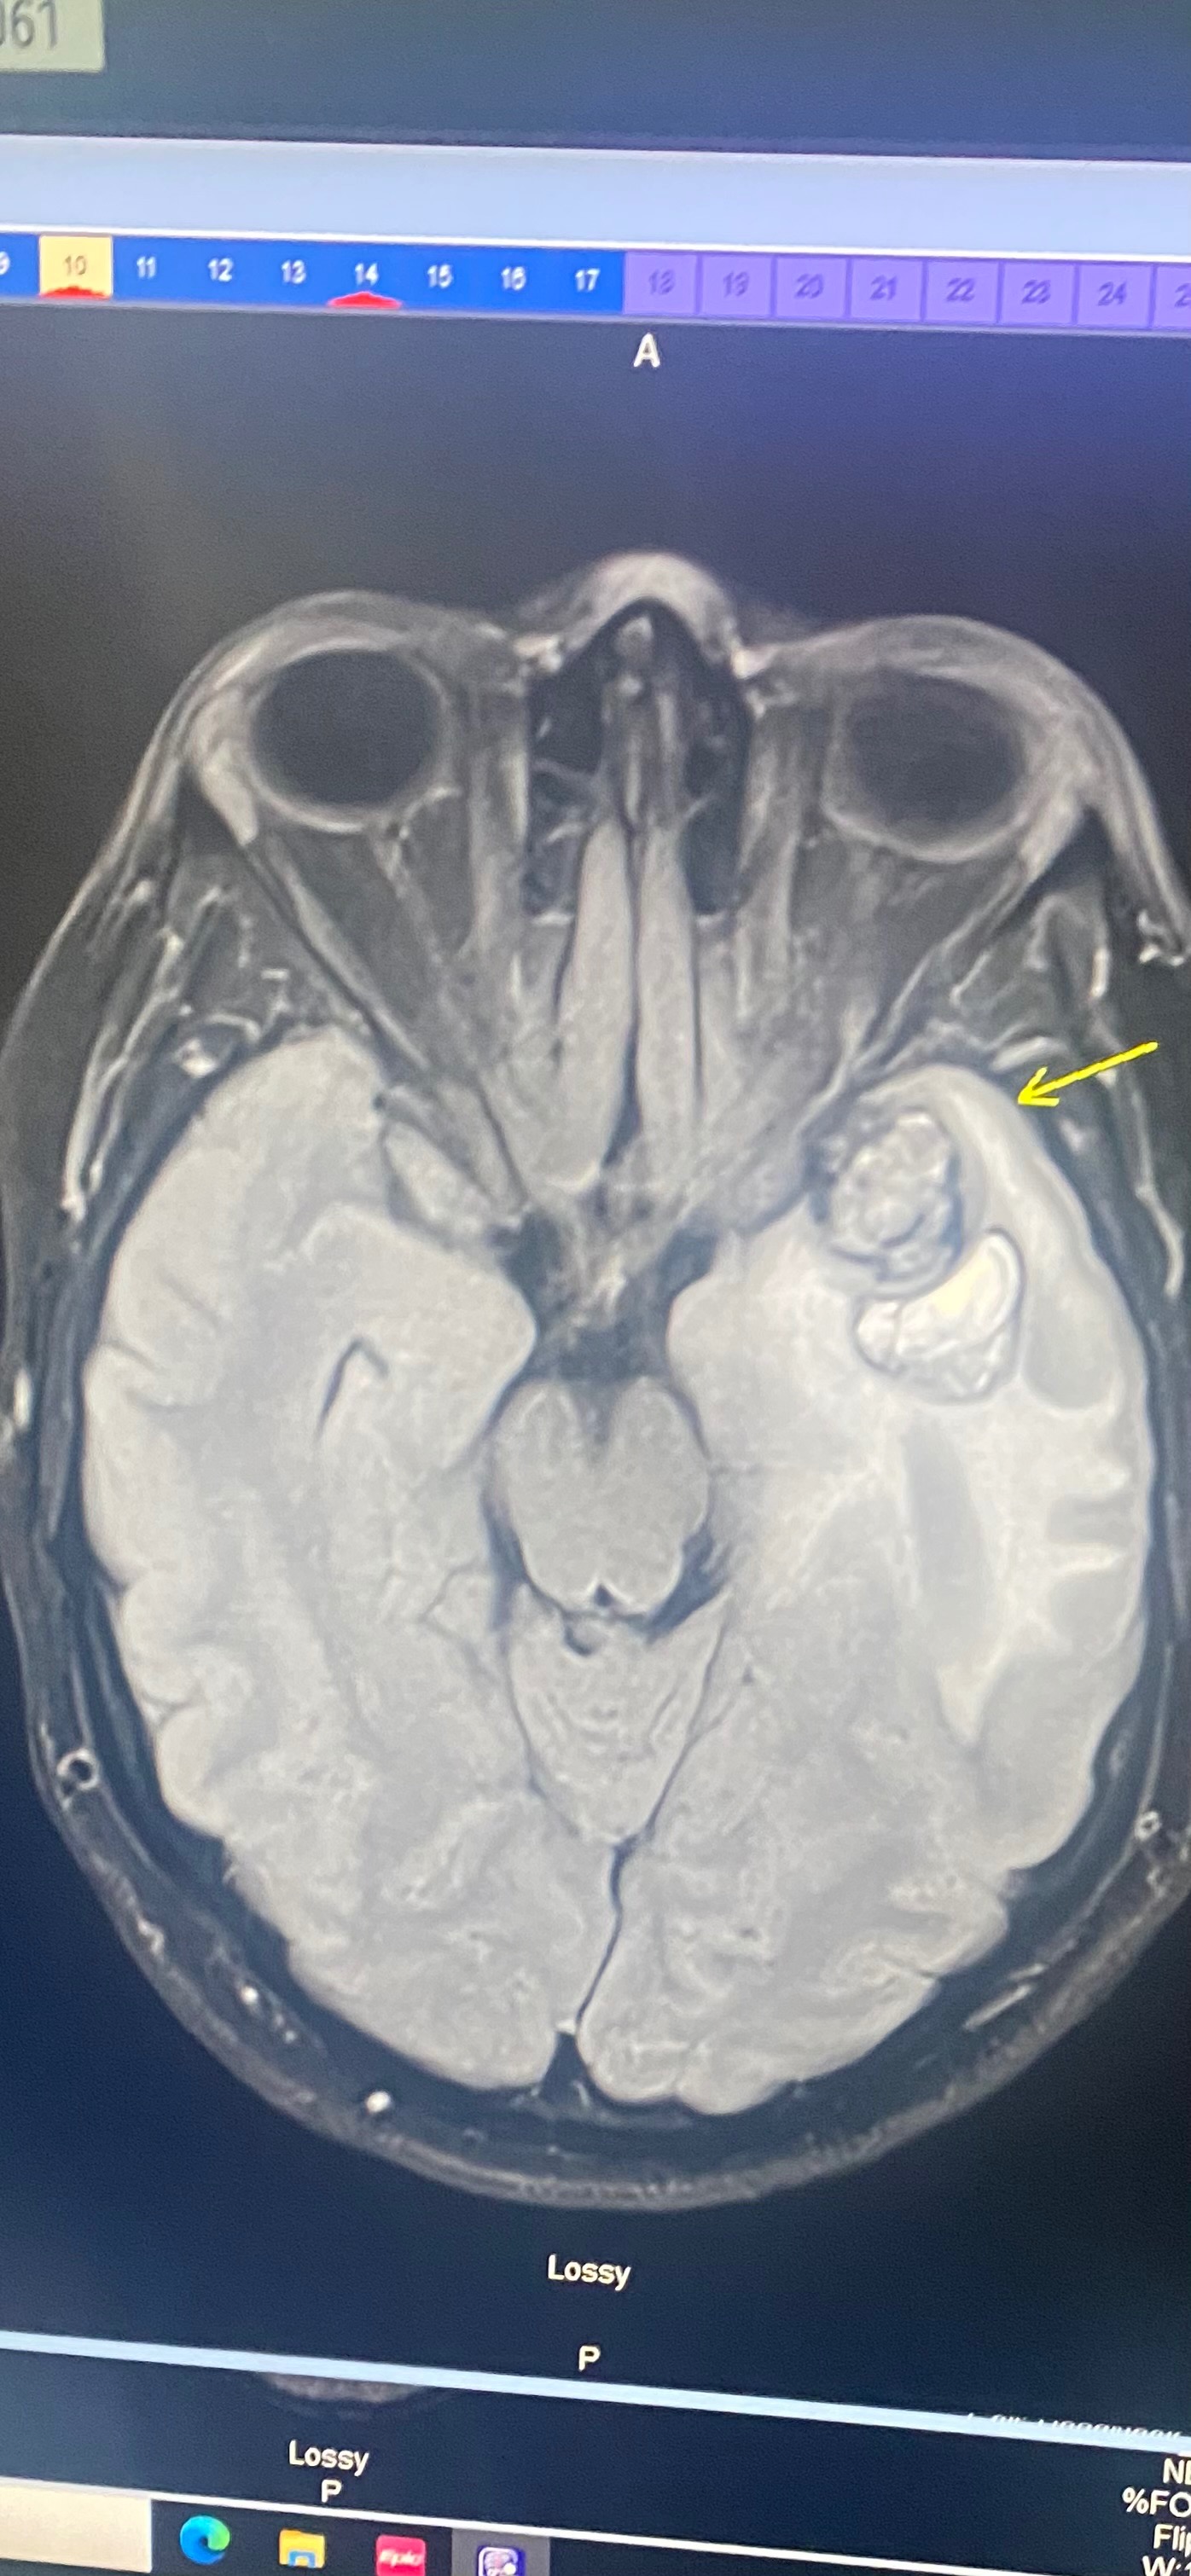

Hello my name is Brittany, if we haven’t met, please know my family is everything to me! On July 9th, 2025 I received a call that shook my world. My cousin, Samantha Bennett Roberts, had been admitted to North East GA medical center with a 3.2 centimeter malignant tumor. This very rare mesenchymal tumor was in her left temporal lobe and was removed 5 days later by an emergency craniotomy. The last month and a half has brought many different obstacles for her. Including not being able to return to work, travel expenses for medical appointments, and medical costs. Not to mention unforeseen future expenses. Right now our main goal is to keep Samantha from stress. As we all know these kind of things take a toll. I’m creating this Go Fund me to help my cousin through this next phase of her recovery. She has a long road ahead but with our faith and support from our family and friends I know this will make that a bit easier for her! If you prefer to give directly to Samantha please reach out to me and I will direct you how to do so. 3214317601